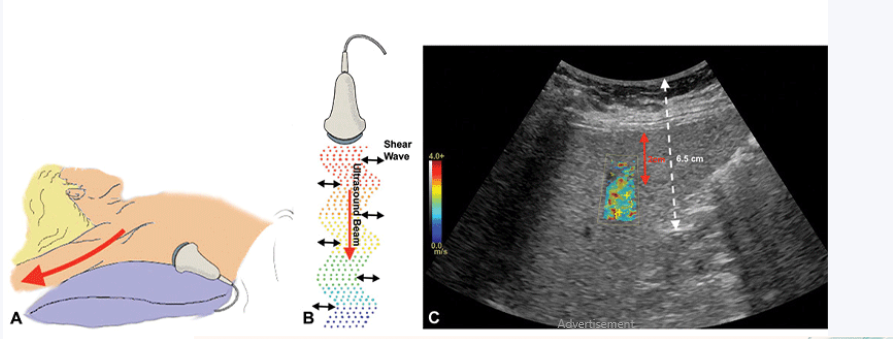

A USG Whole Abdomen, also known as an Ultrasound of the Whole Abdomen, is a non-invasive diagnostic imaging test that uses high-frequency sound waves to create real-time images of the organs and structures located within the abdominal cavity.